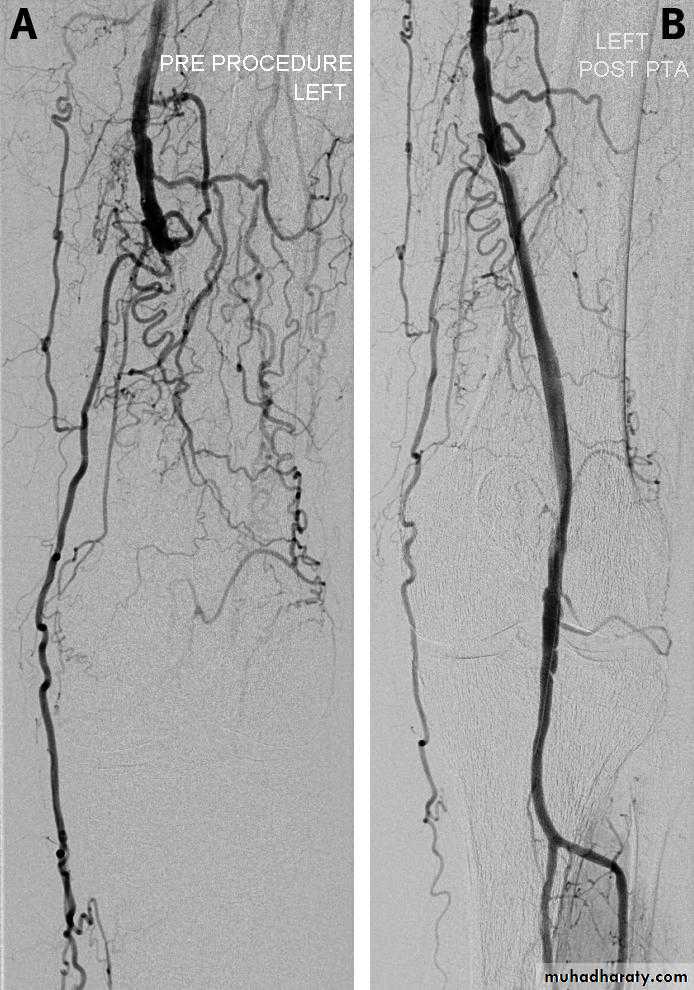

Fig 3 Digital subtraction angiography images taken (A) before and (B) after angioplasty of the left superficial femoral and

popliteal arteries. Note the extensive collateral network typically seen in peripheral arterial disease